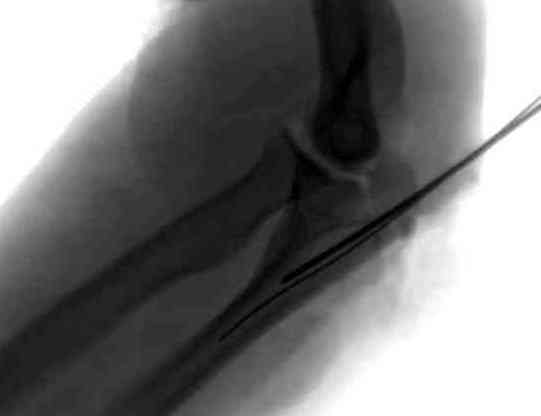

При лечении переломов локтевого отростка положение

больного на операционном столе подсказывается наличием дополнительных переломов, например при переломах таза или ацетабулум предпочтительное положение на спине.

При отсутствии других переломов мы предпочитаем

положение больного на боку, рука на подставке, согнутая в локтевом суставе. Удобно для операторов и легко для рентгенологического контроля.

Предпочитаем обычный стандартный задний доступ, разрез кожи от кончика локтевого отростка на длину

применяемого импланта.

Для доступа к венечному отростку, при наличии перелома локтевого отростка не обязательно проведение дополнительной остеотомии медиального надмышелка.

Обычный стандартный доступ позволяет провести полную ревизию сустава, через фрагменты отломков открывается доступ к венечному отростку и имеется возможность репозиции с окончательной фиксацией. В книге “AO Principles of Fracture Management” описаны методика и варианты фиксации.

Для фиксации перелома локтевого отростка на сегодня множество преконтурных с блокирующими возможностями пластин.

Стабильную фиксацию, особенно при оскольчатых

переломах, можно добиться, применяя технику Bridge Plate, и за счет тех пластин, где имеется возможность проведения множественных шурупов (2.7 мм) проксимально.